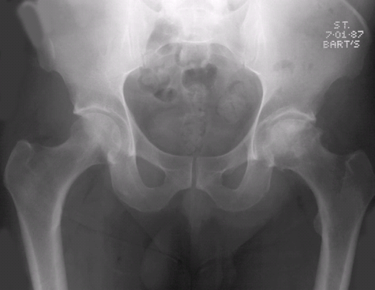

单选题 观察下面X线平片,你的诊断为

A. 左侧股骨头缺血坏死

B. 左侧股骨颈骨折

C. 右侧股骨头缺血坏死

D. 右侧股骨颈骨折